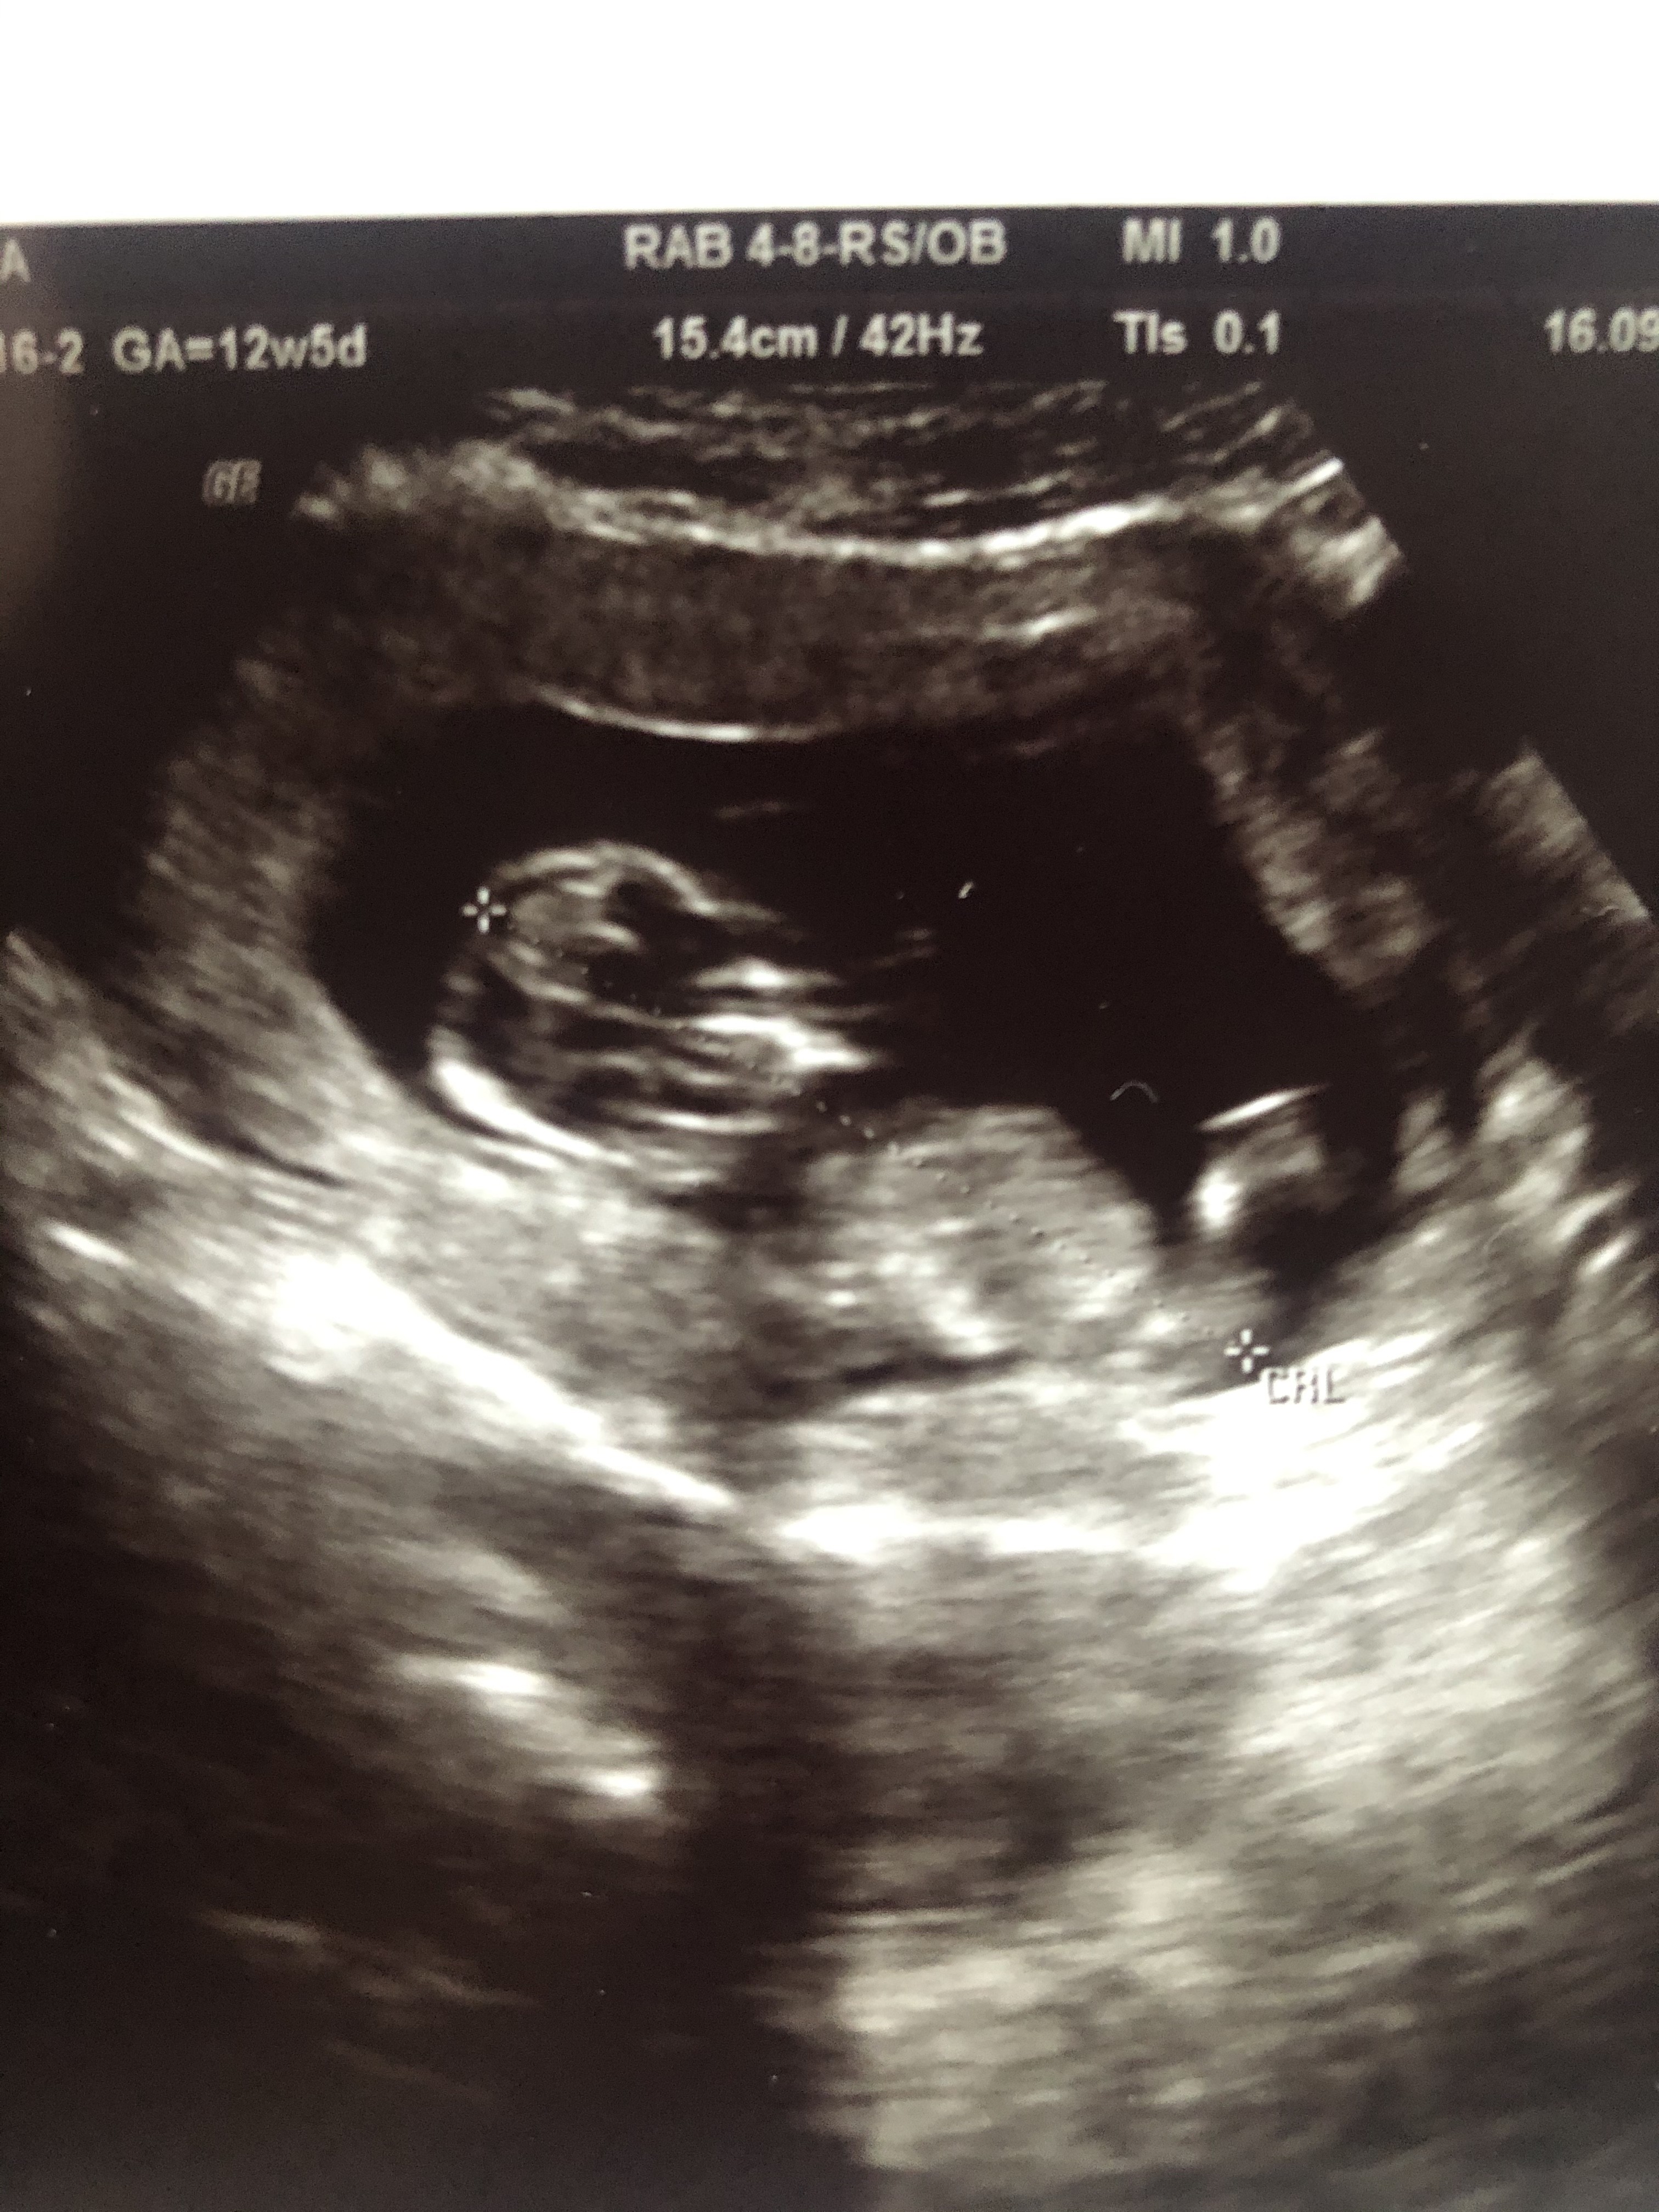

Witam, jestem w 13 tc, czy po tym zdjęciu usg da sie stwierdzić płeć dziecka?

Dzidziuś jest bokiem, wiem, ale chętnie posłucham doświadczonych mamusiek. Lekarz płci nie podał stwierdził, ze jest za wcześnie. Cała reszta badan jest bardzo dobra, dlatego odetchnęłam z ulga:-) Pozdrawiam Mamusie!